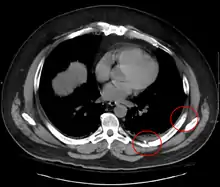

معرض صور